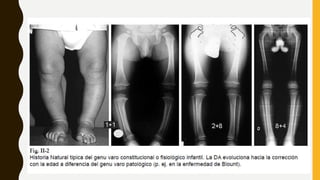

DEL DESARROLLO

• Esta deformidad aparece a partir de los 3 años de

edad.

• Antes de alcanzar el eje en valgo fisiológico se

produce un valgo máximo de unos 15°

• Disminuye ligeramente hasta alcanzar los valores

normales en tomo a los 8 años.

• En el 95% de los casos mejorará de forma

espontánea.